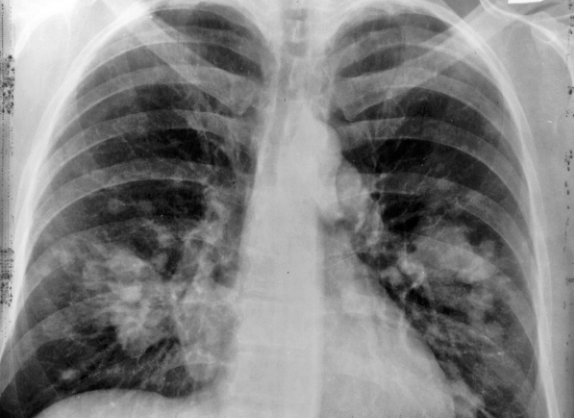

Kanser veya mantar gibi rahatsızlıkların belirtisi olabilen bu rahatsızlık, yayın olarak görülür. Lekelenme için öncelikle röntgen ve tomografi çekilmelidir. Uzman bu süreçten sonra leke tespit ettiğinde detaylı tetkiklerle ciddi olup olmadığına dair araştırma yapar. Peki akciğer lekelenmesi neden olur?